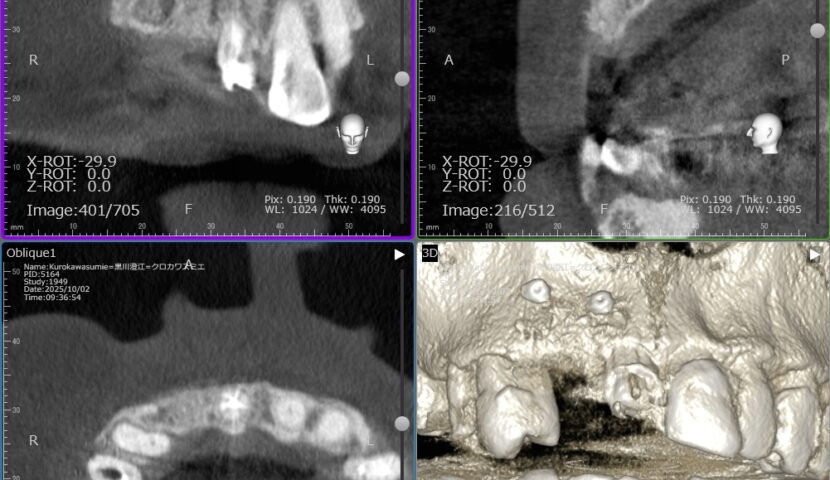

インプラント 症例1 症例2 症例3ガイドサージェリーについて 症例4歯牙移植 症例5 症例6 症例7 症例8